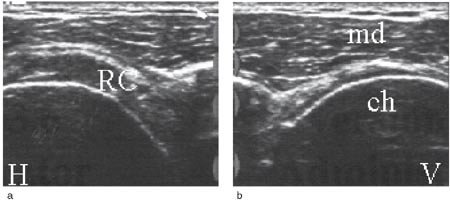

Undersøkelsesgangen er standardisert. Den utføres med pasienten sittende på en roterbar krakk og undersøkeren stående bak. Vi har fem hovedprojeksjoner som fremstiller senene i transversalt og longitudinalt plan og som suppleres med dynamisk undersøkelse. Først utføres to ventrale projeksjoner med armen addusert, og med underarmen supinert, liggende på låret (musculus subscapularis, den lange bicepssenen) (fig 2a, b, e-fig 3a, b). Deretter følger to laterale projeksjoner med addusert og innoverrotert arm, og med underarmen bak ryggen (musculus supraspinatus og infraspinatus) (fig 4 a – c og 5a, b). Til slutt utføres den bakre projeksjonen med armen i utgangsposisjon (e-fig 6a, b). Resultatet dokumenteres på laserskriver eller lagres på diskett. Figurene 2 til 6 viser typiske normale funn.

Rotatorcuffrupturer klassifiseres med ultralyd ut fra lokalisasjon, størrelse og grad (partiell, full tykkelse). Hovedlokalisasjonen er distalt i supraspinatussenen ved festet mot tuberculum majus (1). Det er beskrevet tre hoved- og tre tilleggskriterier for ultralydfunn ved cuffrupturer (3, 5). Hovedkriteriene har størst betydning og det kreves påvisning av minst ett av hovedkriteriene i to plan for ultralyddiagnosen rotatorcuffruptur. Sammen med et hovedkriterium støtter hvert av tilleggskriteriene sannsynligheten for diagnosen. Hovedkriteriene er hypoekkoisk defekt (fig 7), tap av konveksitet (fig 8 a, b) og skallet humerushode (fig 9a, b). Hypoekkoisk defekt er typisk for akutte rupturer og representerer en væskeansamling i defekten mellom rupturkantene (1). Tap av konveksitet og skallet humerushode er stadier i en progredierende degenerativ prosess med gradvis skade og retraksjon av rupturendene og herniering av bursavev og deltoidmuskel i defekten.